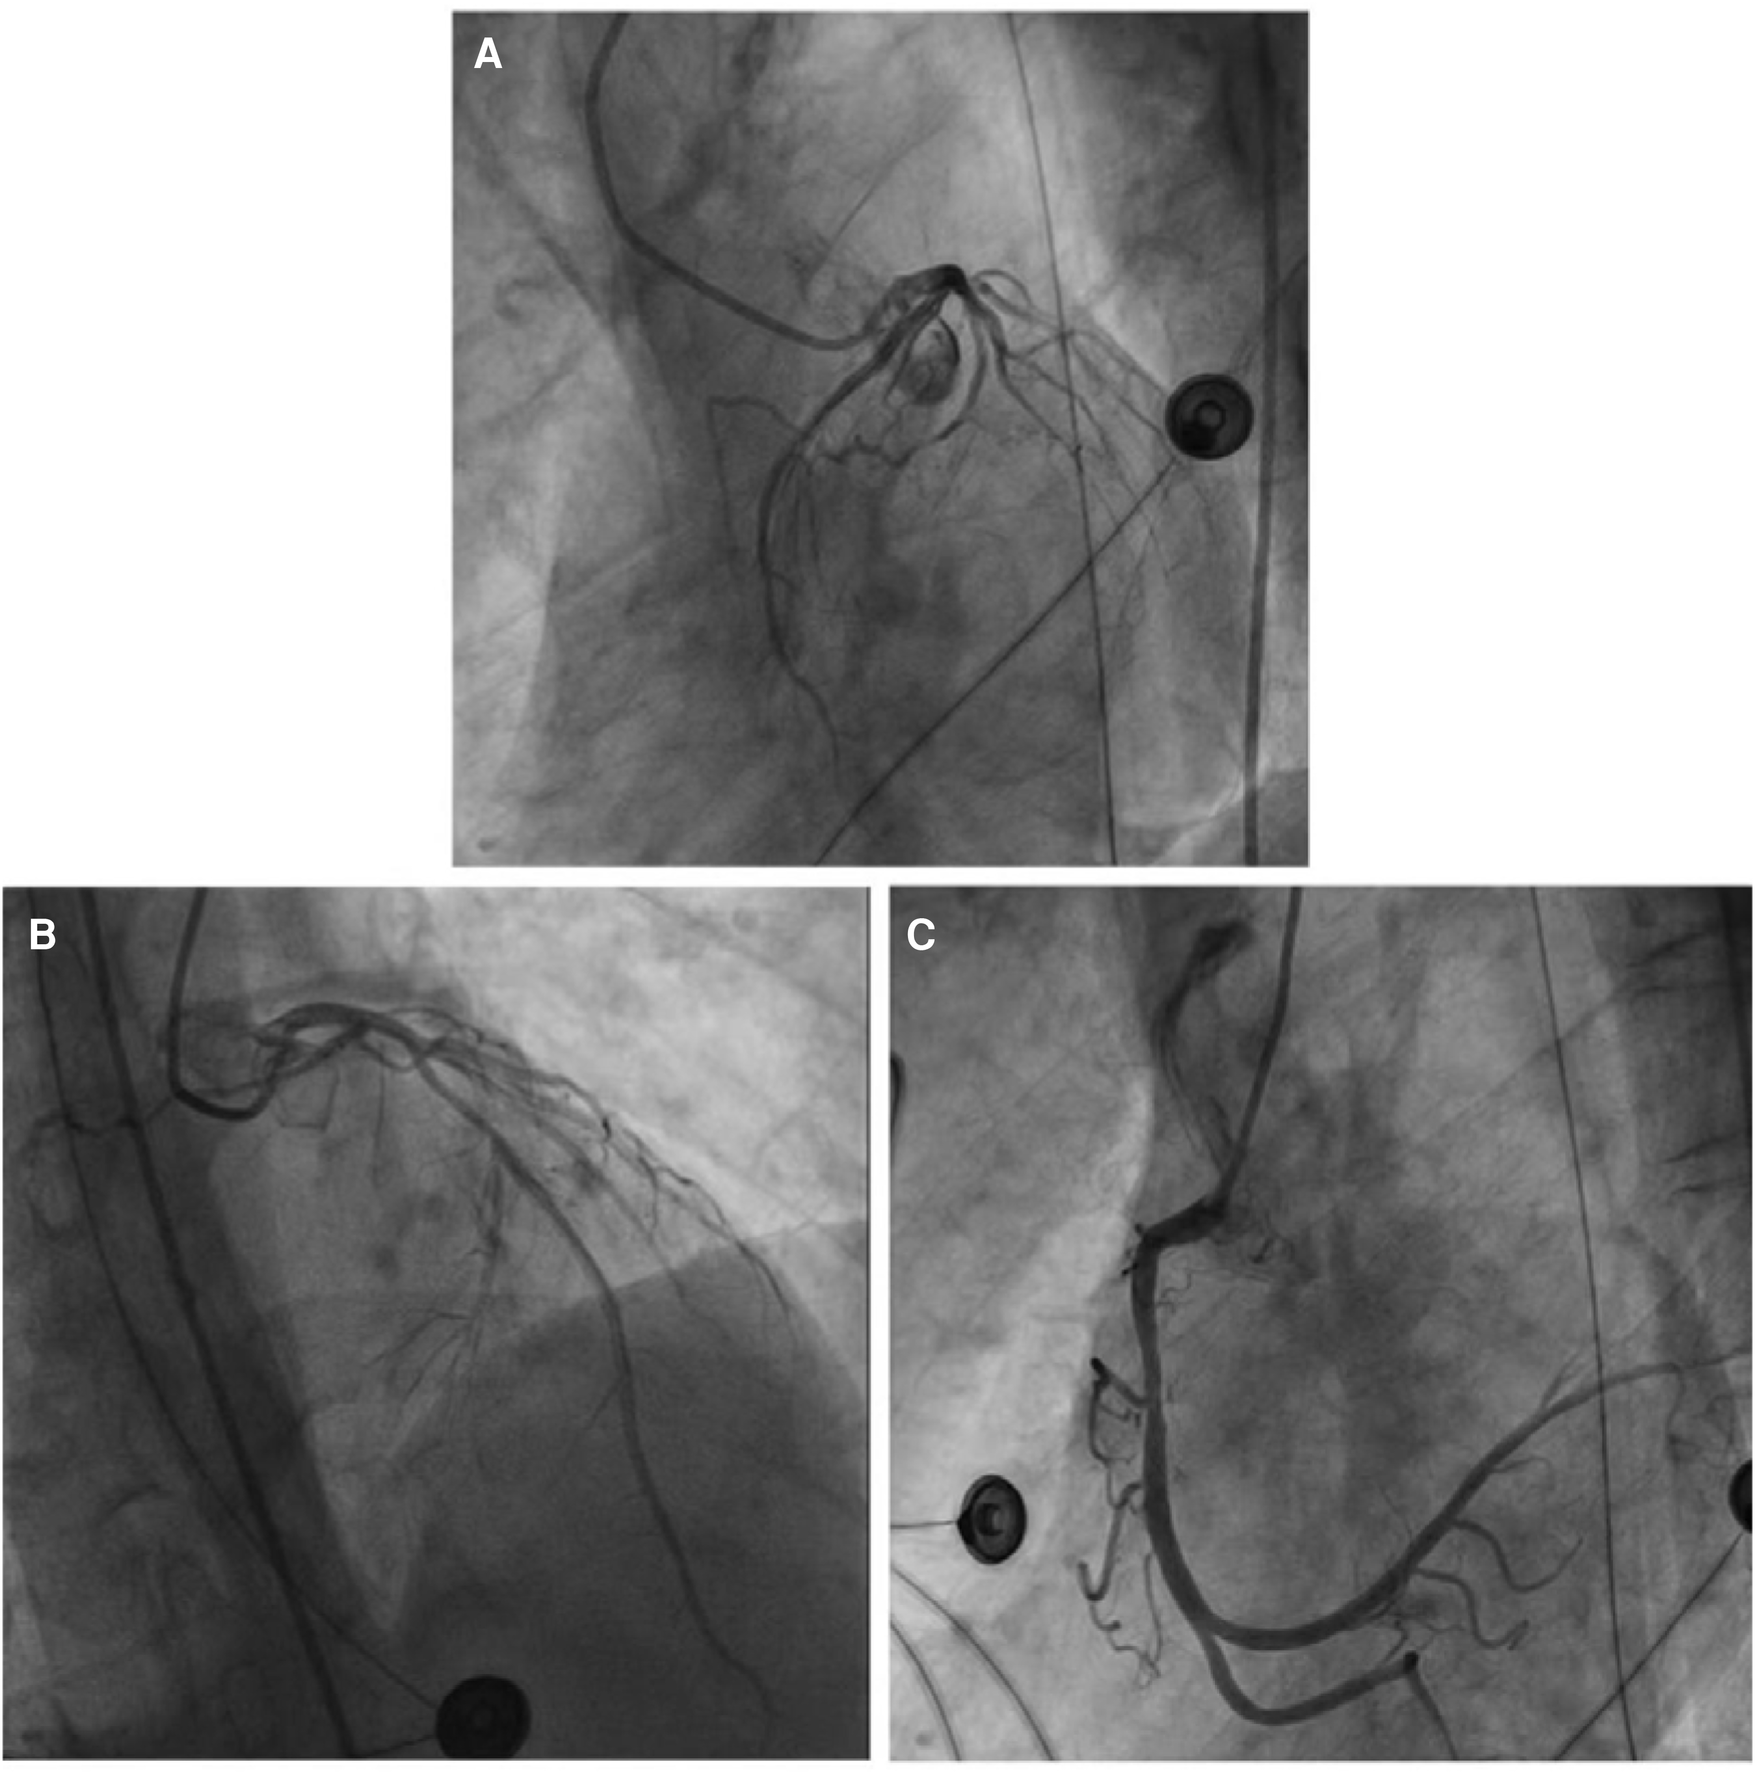

Emergency coronary angiography revealed approximately 50% eccentric stenosis in the mid-segment of the left anterior descending coronary artery and approximately 50% eccentric stenosis in the mid-segment of the right coronary artery, with no significant abnormalities in other vessels (Figure 5). Following the coronary angiography procedure, the patient returned to the ICU for further treatment. Hemodynamic monitoring showed: cardiac output (CO) of 3.4 L/min, cardiac index (CI) of 1.9 L/min/m2, stroke volume (SV) of 27 ml, stroke volume index (SVI) of 16 ml/m2, systemic vascular resistance (SVR) of 1,250 dynes·s/cm5, systemic vascular resistance index (SVRI) of 2,192 dynes·s/cm5/m2, extravascular lung water (EVLW) of 435 ml, extravascular lung water index (EVLWI) of 6.6 ml/kg, global end-diastolic volume (GEDV) of 828 ml, and global end-diastolic volume index (GEDVI) of 469 ml/m2, consistent with features of cardiogenic shock.

Figure 5

(A) No obvious abnormalities were noted in the left circumflex coronary artery. (B) The most severe segmental eccentric stenosis of about 50% was observed in the middle segment of the left anterior descending coronary artery. (C) The most severe segmental eccentric stenosis of about 50% was observed in the middle segment of the right coronary artery.